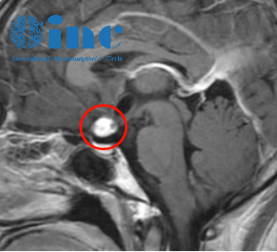

INC出国手术案例之研究生第三脑室海绵状血管瘤

“感谢INC和巴教授把我从绝望中解救出来,以后每一次的诗和远方我都会心怀感恩”

INC成功手术案例之中脑顶盖胶质瘤术后无复发,考上名校

“孩子术后恢复非常好,给我们病友群的病友起了一个很好的示范作用。我一些中脑胶质瘤患者现在都在存钱,万一需要手术大家还是想要去找巴教授。”